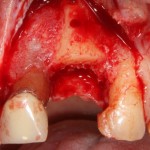

Давайте внимательно посмотрим на состояние лунок центральных резцов после удаления:

Приемлемый фенотип (сочетание толщины и ширины участка жевательной десны) — это, конечно, приятно. Но гораздо важнее сосредоточиться на рисках, их на этот момент два:

— травматическое повреждение слизистой, вызванное удаление зубов связано с тем, что при хроническом воспалении слизистая оболочка теряет эластичность, поэтому легко рвётся. Такая ситуация создаёт серьёзную угрозу эстетическому результату лечения, в зависимости от того, насколько быстро десна придёт в норму.

— как и предполагалось после КЛКТ, утрата костной стенки привела к тому, что десна провалилась в просвет лунки левого центрального резца. Это еще больше усугубляет клиническую ситуацию.

Для нас это не было неожиданностью. Зная закономерности изменений тканей при хроническом  воспалении и данные КЛКТ, мы можем довольно точно предсказывать развитие клинической ситуации и соответственно к ней подготовиться. Именно поэтому, помимо обычной немедленной имплантации, мы запланировали аугментацию лунки с помощью биоматериалов и метода трансплантации лоскута (см. предварительные планы лечения).